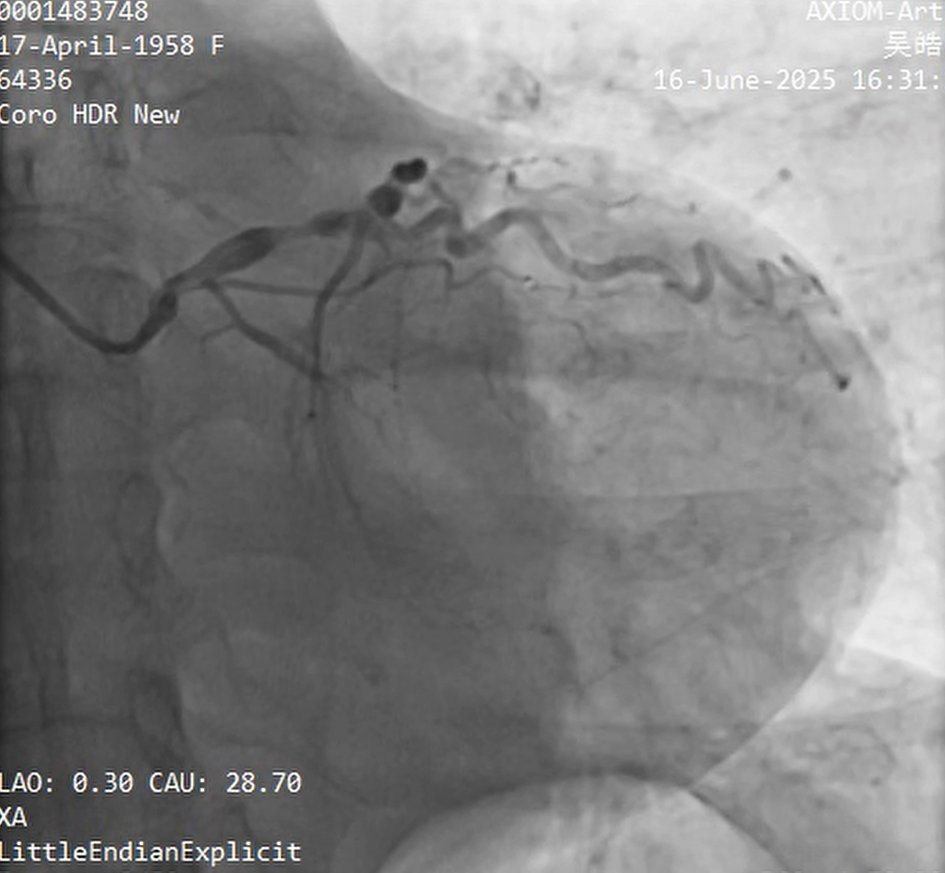

Relevant Catheterization Findings

30% stenosis in LMT; 100% stenosis in LCX£»99% stenosis with calcification in the LAD£»99% stenosis in the RCA¡£